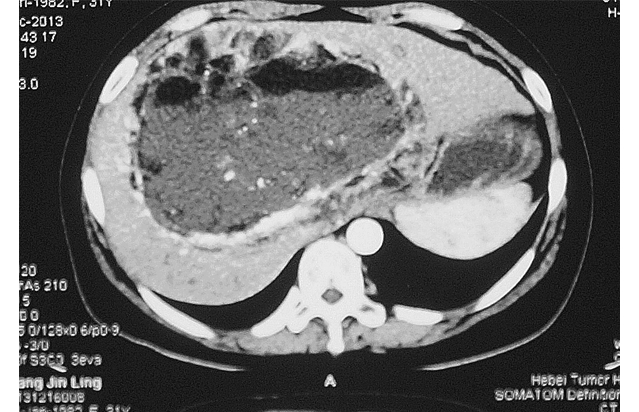

患者,女,31岁。于2013年3月4日查体发现肝脏肿物1月入院。无腹胀、腹痛、腹泻、发热等任何不适主诉。饮食正常,二便正常,体重无变化。查体:皮肤黏膜无黄染,无肝掌、蜘蛛痣。全身浅表淋巴结未触及。右肋部膨胀饱满,肝脏下缘位于右肋缘下约8 cm,剑突下5 cm,质地较软,边缘钝厚,表面无结节感,无压痛、触痛或叩痛。腹部移动性浊音(-);双下肢无水肿。辅助检查:上腹部CT示肝内巨大不均匀肿物,密度不均,内可见脂肪密度,不均匀强化,考虑肝脏巨大血管平滑肌脂肪瘤,见图 1。甲乙丙肝炎抗体均(-)。肝功能检查:正常;肿瘤标志物:AFP、CA199均在正常范围。2013年3月8日于我院行“剖腹探查术”:术中可见肝十二指肠韧带后方约20 cm×16 cm×16 cm巨大肿物,与肝门、肝左右叶、下腔静脉粘连,不能剥离,遂切除部分肿物送病理检查。术后病理结果:混合型脂肪肉瘤(上皮型与多形型之间过渡)。基于肿瘤巨大与周围组织粘连严重,无法手术切除,遂采取介入治疗,选择肝脏肿瘤供血动脉行灌注化疗及栓塞治疗。2013年4月9日第一次介入术中血管造影显示:肝动脉受压、移位、迂曲、增粗,实质期肝内可见巨块状肿瘤染色,由肝动脉及两侧膈动脉供血,肿瘤染色明显,肿瘤血管丰富交织呈网状,门静脉显影清晰,见图 2A、B。灌注化疗药物选择阿霉素、异环磷酰胺、达卡巴嗪;栓塞剂选择碘油、明胶海绵颗粒或海藻酸钠微球混合栓塞,术中患者均无不适。患者至2013年12月16日共行介入治疗6次,2014年1月20日复查CT示:肝脏肿瘤绝大部分液化、坏死,强化减轻,见图 3。血管造影示:肿瘤血管减少,血流量减少。随访:患者目前生存状态良好,无任何不适。

| Figure A and B showed hepatic artery was compressed,shifted,tortuous and thickened,Obvious intrahepatic massive tumor in parenchymal phase,blood supplied by the hepatic artery and bilateral phrenic artery 图2 肝脏原发性脂肪肉瘤患者第一次介入术中血管造影情况 Figure 2 The angiography in first interventional therapy on the patient with liver primary liposarcoma |